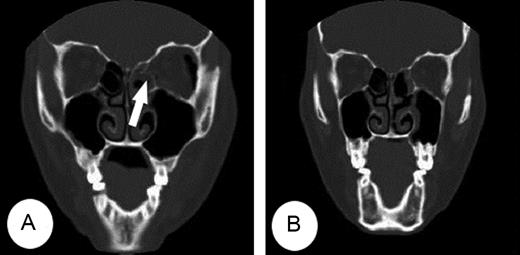

A 38-year-old woman presented diplopia with left lateral gaze after sustaining trauma to the left orbit. There was mild periorbital edema and ecchymosis at presentation. Ophthalmologic examination results were within normal except of ocular motility revealed an abduction deficit in the left eye (Fig. 1A). Computed tomography (CT) demonstrated a trapdoor-type left medial orbital wall fracture with entrapment of the medial rectus muscle (Fig. 2A). She was immediately taken to the operating room and underwent surgery under general anesthesia. Endoscopic endonasal reduction surgery for medial blowout fracture, first introduced by Yamaguchi [3] was used to expose the fractured medial orbital wall. The entrapped medial rectus muscle and herniated orbital tissue were gently released from the fracture after ethmoidectomy. The herniated orbital tissue and fractured bone were reduced to the original position, and then supported with a suitably sized Silastic sheet placed in the ethmoid sinus in an inverse U shape. A piece of Merocel® was packed between the Silastic sheets to provide support and prevent orbital tissue herniation, which were removed 4 weeks later at out-patients clinic (Fig. 3). The patient's ocular symptoms completely resolved 3 days postoperatively (Fig. 1B). Computed tomography scans demonstrated that the medial rectus muscle was reduced after surgery (Fig. 2B).

(A) Left ocular movements showed prominent limitation of abduction preoperatively. (B) After surgery, ocular movement was completely improved.

(A) CT showed a trapdoor fracture of the left medial orbital wall with the medial rectus muscle entrapped (arrow) within the fracture. (B) The entrapped medial rectus muscle and fractured medial wall were resolved on post-operative CT.